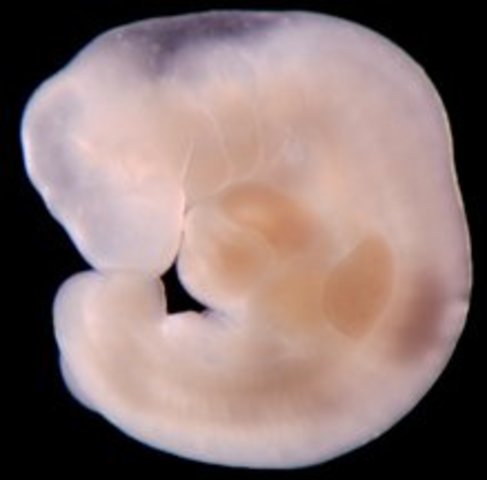

• Week 3: Cells Join, Divide- New Life Begins

Week 3: Cells Join, Divide- New Life Begins

The fertilized egg will attach to the lining of the uterus.

• Week 4: Implantation

Week 4: Implantation

The egg is called a blastocyst at the stage in pregnancy. At this stage the baby is barely the size of a pinhead. It also releases a hormone into the bloodstream called human gonadotrophin hormone (hCG).